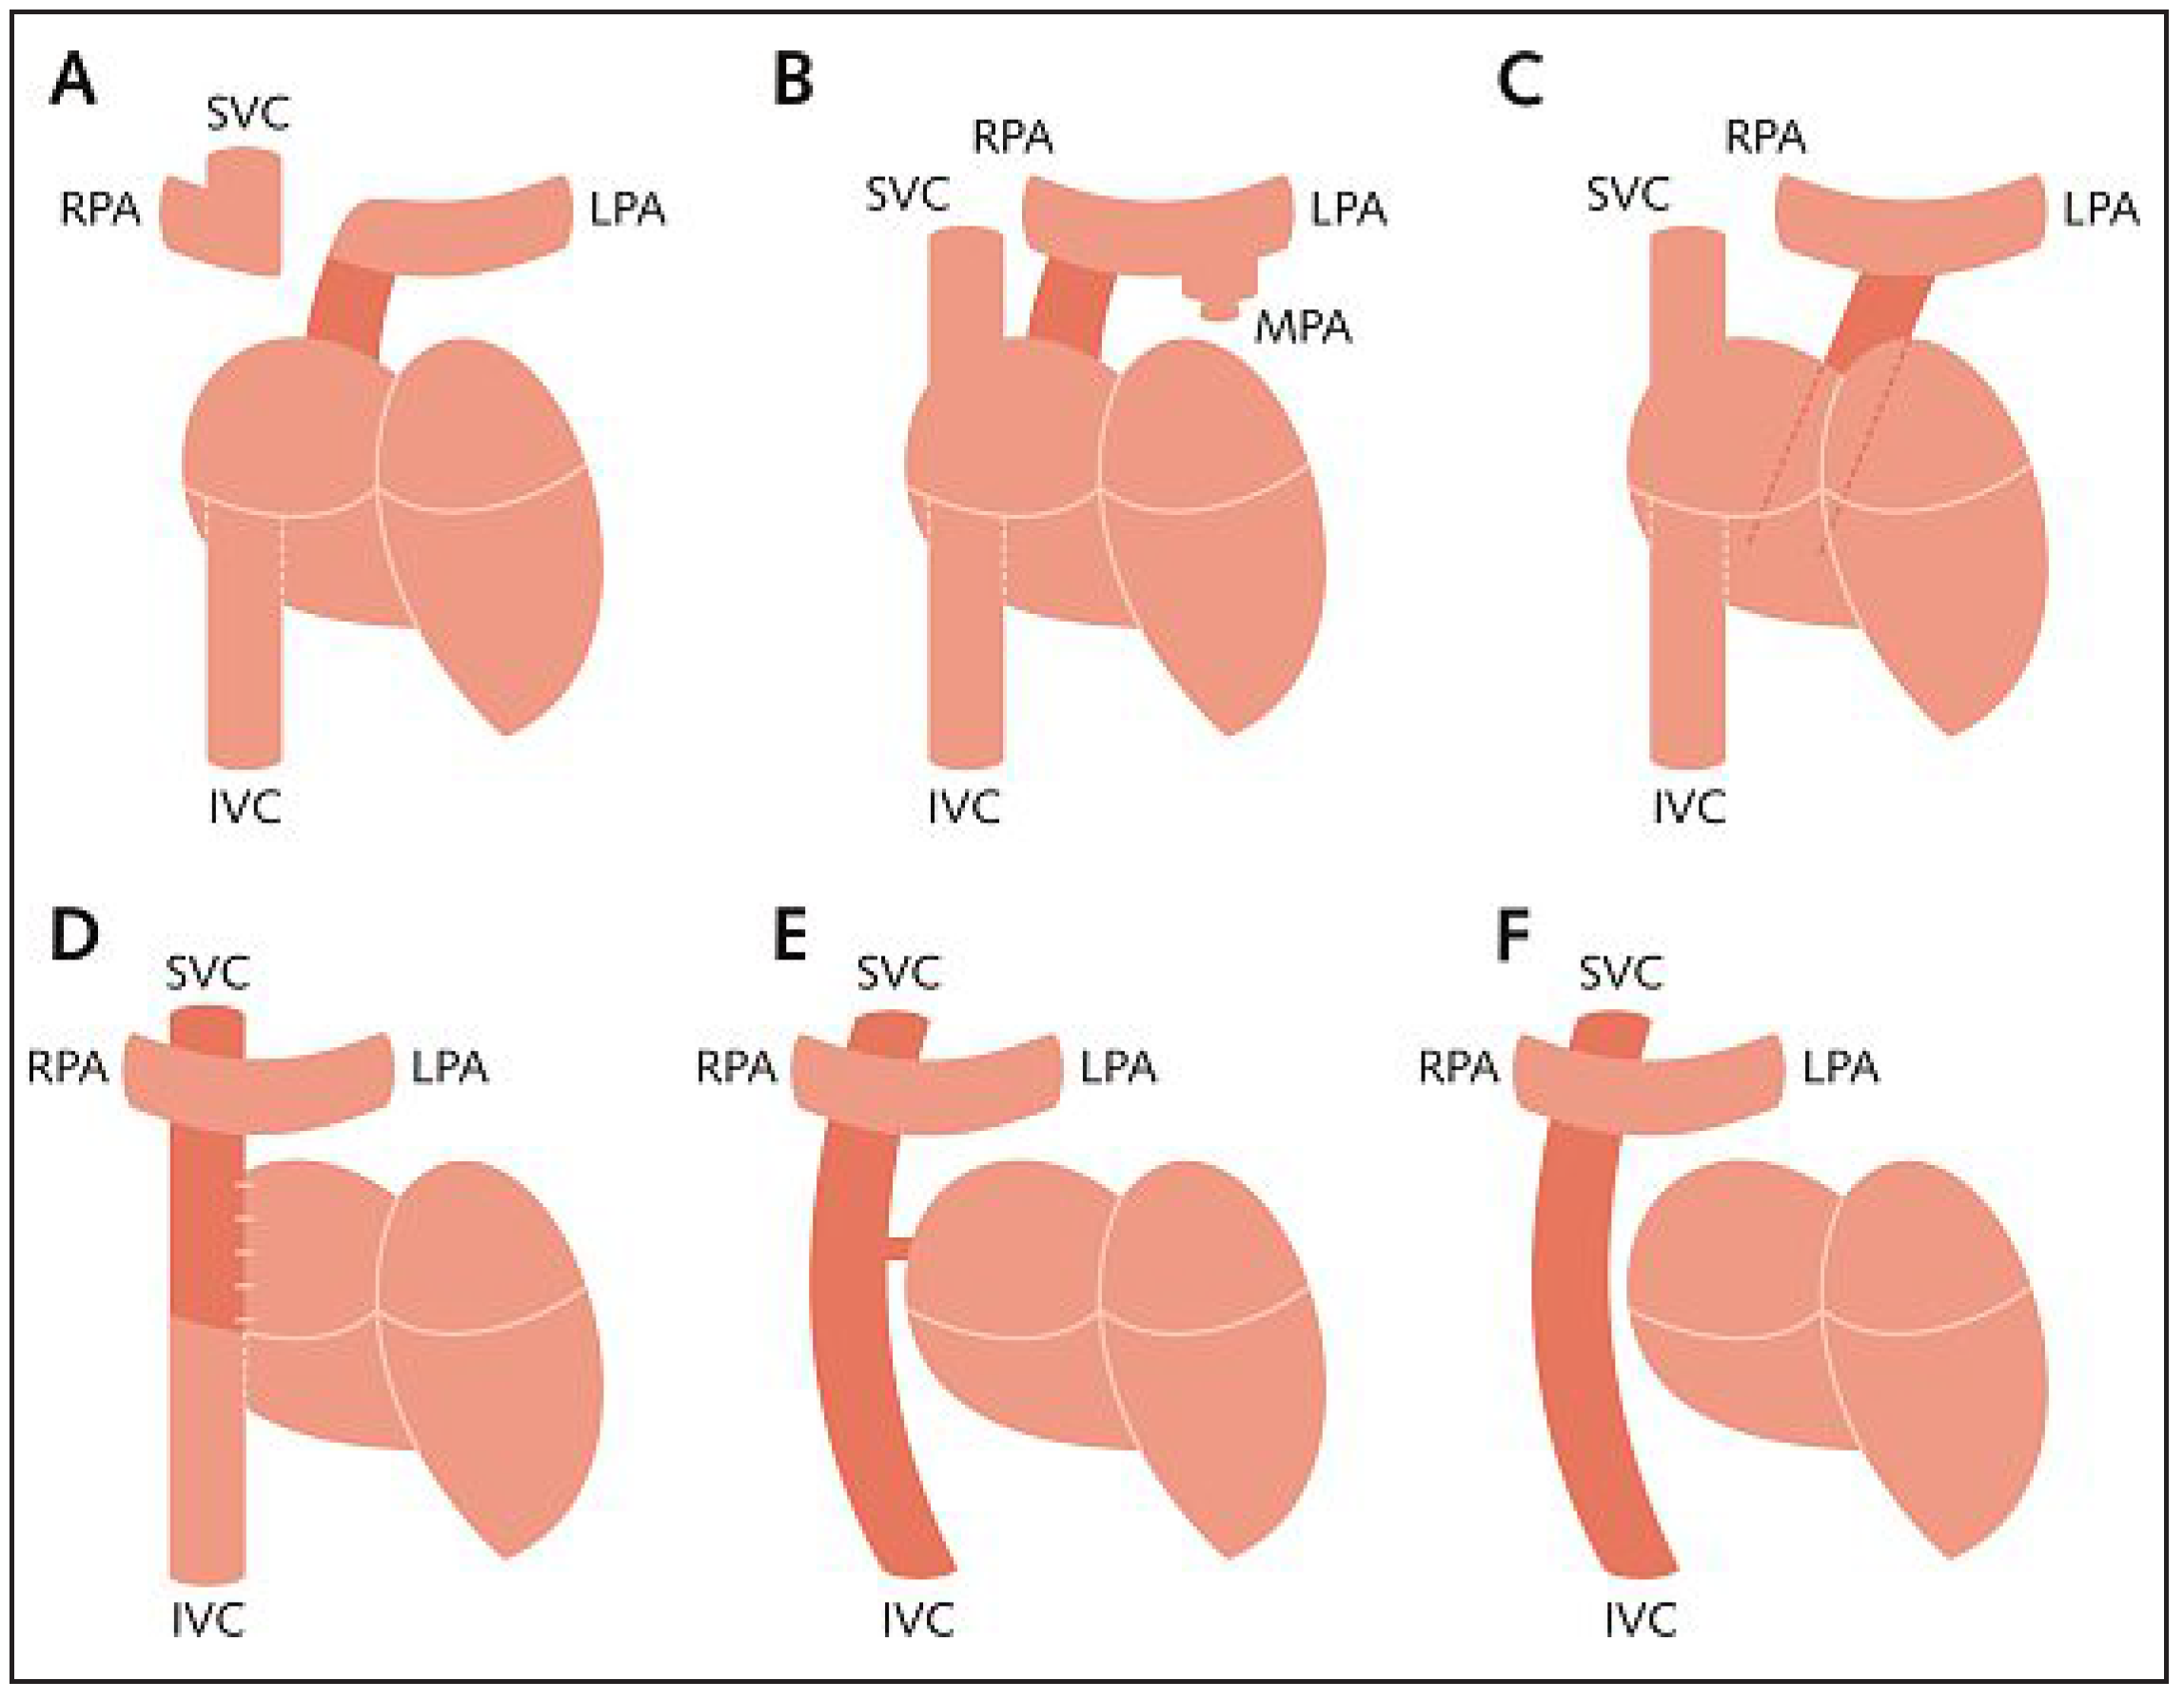

Abbildung 1.

Schematische Darstellung der verschiedenen Typen von möglichen Fontan-Zirkulationen. A Originale Fontan-Operation mit oder ohne klappentragende Anastomosen des rechten Vorhofes mit der linken Pulmonalarterie sowie der Vena cava superior mit der rechten Pulmonalarterie, unter Ligatur der Pulmonalisbifurkation. B Atrio-pulmonale Anastomose nach Kreutzer mit Anastomose des rechten Vorhofohres mit der rechten Pulmonalarterie. C Atrioventrikuläre Anastomose nach Björk bei Trikuspidalatresie. D Intrakardialer lateraler Tunnel mit Anastomose der Vena cava inferior zur rechten Pulmonalarterie. E Extrakardiale totale cavo-pulmonale Anastomose mittels Conduit (TCPC) und Fenestrierung. F TCPC ohne Fenestrierung. SVC = Vena cava superior; IVC = Vena cava inferior; RPA = rechte Pulmonalarterie; LPA = linke Pulmonalarterie; MPA = Truncus pulmonalis.

Abbildung 1.

Schematische Darstellung der verschiedenen Typen von möglichen Fontan-Zirkulationen. A Originale Fontan-Operation mit oder ohne klappentragende Anastomosen des rechten Vorhofes mit der linken Pulmonalarterie sowie der Vena cava superior mit der rechten Pulmonalarterie, unter Ligatur der Pulmonalisbifurkation. B Atrio-pulmonale Anastomose nach Kreutzer mit Anastomose des rechten Vorhofohres mit der rechten Pulmonalarterie. C Atrioventrikuläre Anastomose nach Björk bei Trikuspidalatresie. D Intrakardialer lateraler Tunnel mit Anastomose der Vena cava inferior zur rechten Pulmonalarterie. E Extrakardiale totale cavo-pulmonale Anastomose mittels Conduit (TCPC) und Fenestrierung. F TCPC ohne Fenestrierung. SVC = Vena cava superior; IVC = Vena cava inferior; RPA = rechte Pulmonalarterie; LPA = linke Pulmonalarterie; MPA = Truncus pulmonalis.

Seit der ersten Publikation von Fontan und Baudet im Jahre 1971 haben sich die chirurgischen Möglichkeiten, eine Fontan-Zirkulation anzulegen, entscheidend weiterentwickelt (Abb. 1). Wurden bei den ersten Fontan-Patienten noch eine unidirektionale obere cavo-pulmonale Anastomose («klassische Glenn-Anastomose») sowie klappentragende Anastomosen zwischen der VCI und der atrio-pulmonalen Konnektion durchgeführt (Abb. 1A), setzte sich eine technisch einfachere und weniger komplikationsträchtige Variante nach Kreutzer (wie bei unserer Patientin) für die folgenden Jahre durch. Hierbei wurde lediglich der rechte Vorhof mit dem Truncus pulmonalis anastomosiert (Abb. 1B). Nach weiteren Modifikationsschritten wird heutzutage der rechte Vorhof umgangen und das Blut der VCI durch einen extrakardialen Conduit direkt in die Pulmonalarterie geleitet (Abb. 1E, 1F). Die «Fontan-Zirkulation» wird dabei stufenweise erreicht. Falls nötig wird beim Neugeborenen mit komplexem Herzfehler als Erstes eine pulmonale Hyperperfusion durch Bändelung der Pulmonalarterien oder eine pulmonale Hypoperfusion durch Anlage einer aorto-pulmonalen Verbindung (z.B. modifizierter Blalock-Taussig-Shunt) korrigiert. Als nächster Schritt wird im Alter von 3–6 Monaten zur Vorbereitung der Fontan-Zirkulation bidirektional eine Anastomose zwischen VCS und rechter Pulmonalarterie angelegt. Als letzter Schritt erfolgt im Alter zwischen 2 und 3 Jahren die Implantation eines extrakardialen Conduits zur Konnektion der VCI und der Pulmonalarterie mit der resultierenden kompletten Trennung des venösen und systemischen Kreislaufes.